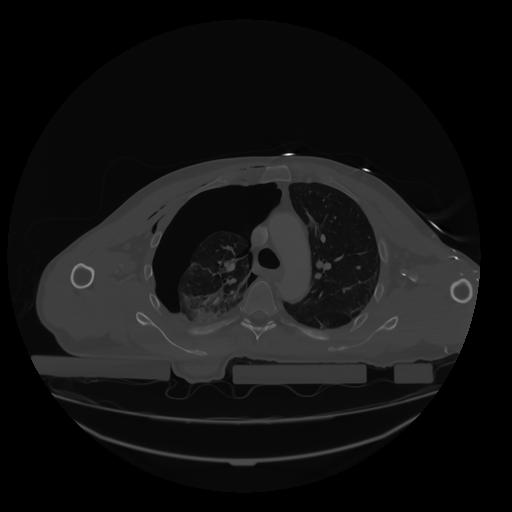

28 CUERPO,CE,Vol,2.0,CUERPO,,